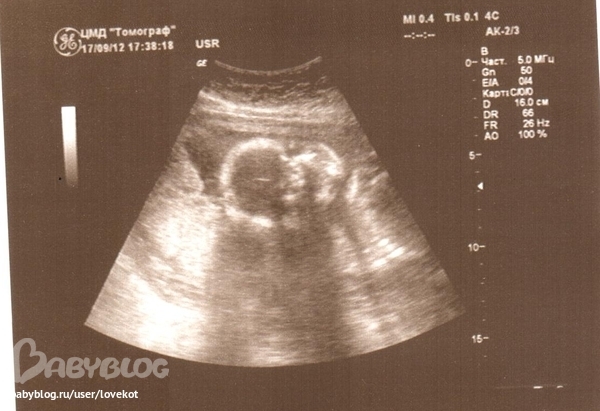

ну вот... пуповина у нас между ножек))

ток кто меня там пинает не ясно)) зато хоть немного успокоили ,что плацента все же поднимается)) и патологий нет))

а вот кисту не видно!